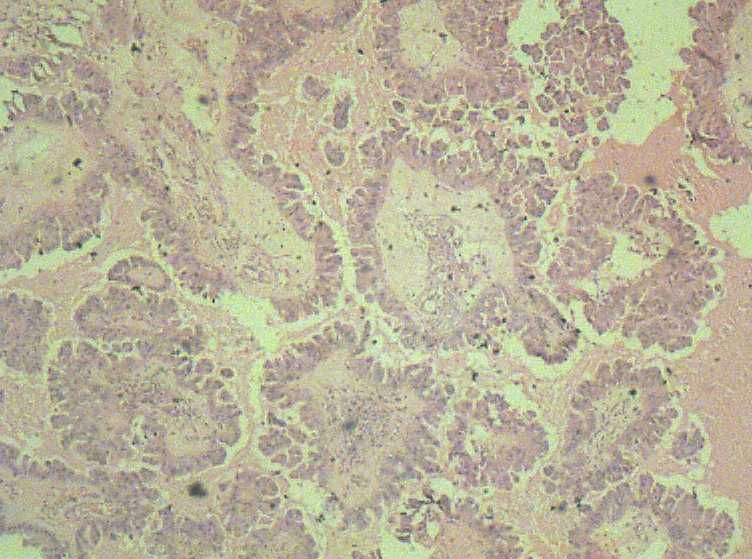

女,27岁,剖宫产术中见一侧卵巢一肿物。大体:椭圆形肿物大小3*2*1.5表面光滑,剖开内容为浅黄色胶状物,质均,囊内壁较光滑,部分见细小乳结构。

可见增生的上皮,形成乳头或微乳头,见到钉突和出芽式的生长,漂浮的上皮细胞簇,细胞核轻-中度不典型增生。

从所给的图片来看,发交界性浆液性乳头状囊腺瘤,仔细找找是否有微浸润的存在,再排除浸润成为癌的可能性。

交界性是最低的,还要看看有无更严重的地方,多取材好全面评估。

有乳头的部位 基本都有取到了 。看来报个交界性不是问题了。谢谢各位老师的意见!

曾看到过一个课件,说交界性成分在整个肿瘤中所占的比例要超过10%,不到10%的话仍视为良性。